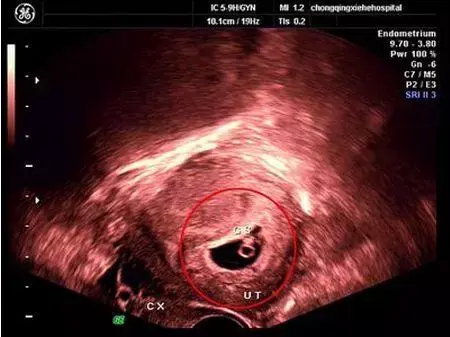

能看出孕囊呢?

一開始孕囊是很細小的,然后再慢慢地長大。一般情況下,懷孕5周以后,B超可看見小胎囊,胎囊約占宮腔不到1/4,或可見胎芽。

如果是正常的宮內妊娠,懷孕40天左右可以通過B超在子宮內看到孕囊,不過因個體差異而受孕時間的早晚,有的孕婦會推遲至45天左右時才能看到。